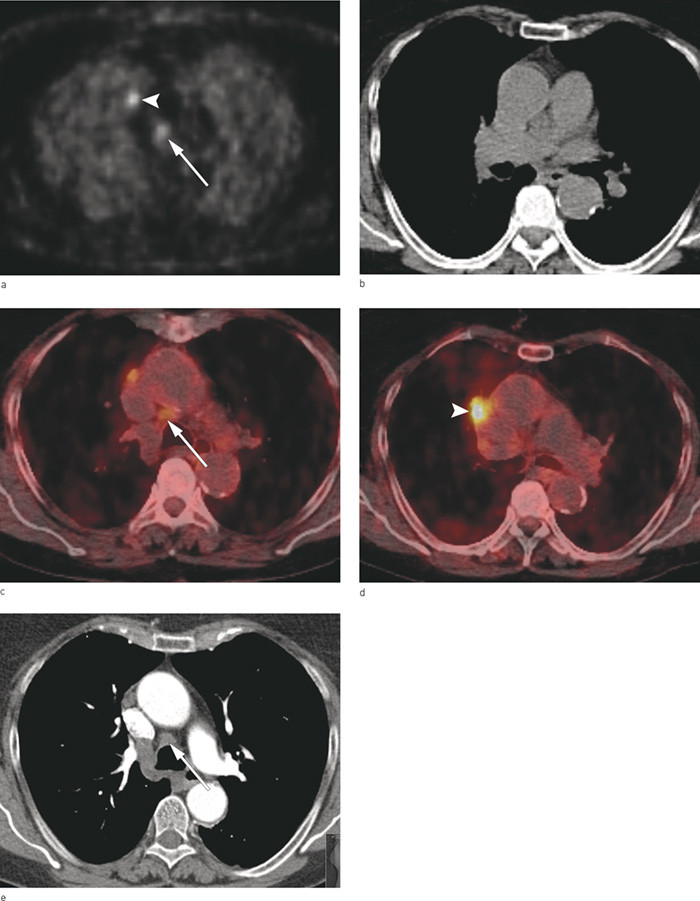

Figure 3a – e Patient with a 2.3 cm squamous cell carcinoma in the right upper lobe close to the mediastinum was examined…

Figure 3a – e Patient with a 2.3 cm squamous cell carcinoma in the right upper lobe close to the mediastinum was examined with 18F-fluoro-2-deoxyglucose (FDG) positron emission tomography (PET) combined with computed tomography (CT) in the same session. Pathological uptake of FDG in PET (a) in primary tumour (white arrowhead) and a lymph node (white arrow) in the mediastinum. The PET image is fused with low dose CT (b) into an integrated PET-CT image which provides both a functional and an anatomical picture of high uptake of FDG in the lymph node (c, arrow) and primary tumour (d, arrowhead). Diagnostic CT with intravenous contrast medium (e) performed in the same session shows anatomical structures including the lymph node (white arrow) in more detail. Fine-needle aspiration cytology of the lymph node obtained by endobronchial ultrasound showed malignant cells (spread to N2 nodule, ipsilateral side). cTNM = T2aN2M0, Stage IIIA